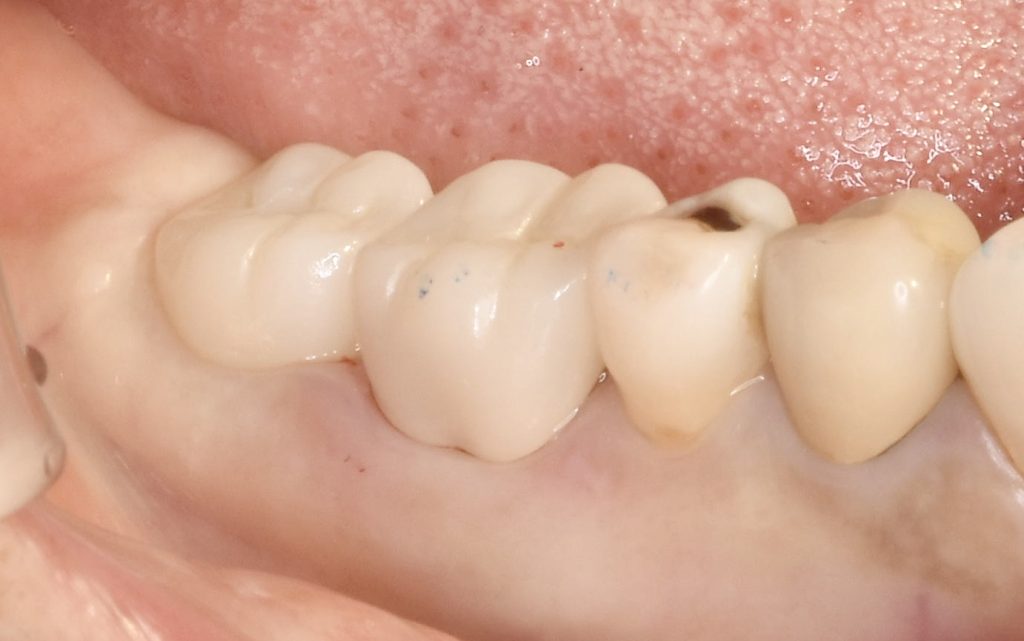

今回、古いメタルインレーの中でカリエスが進行し、骨縁下まで進行していました。

抜歯と同時にインプラント埋入手術を行い、4ヶ月ほどで治療を完了いたしました。